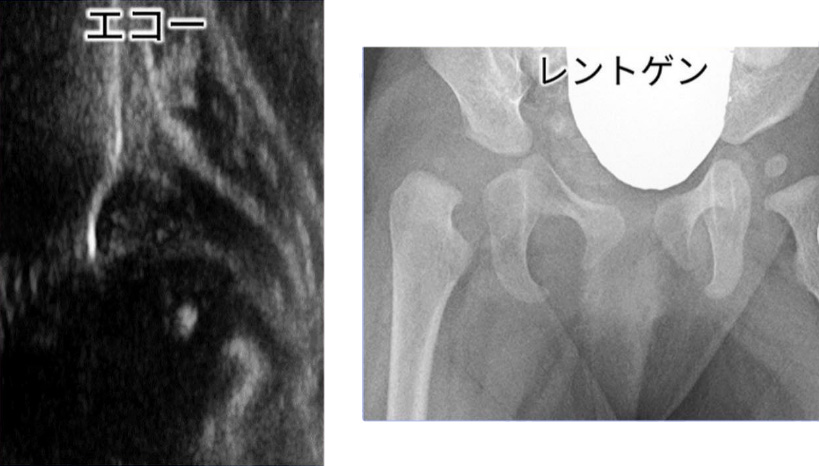

発育性股関節形成不全を診断するための検査方法にはエコー(超音波)とレントゲンがあります。

※どちらで診断するかは、クリニックや病院で異なります。